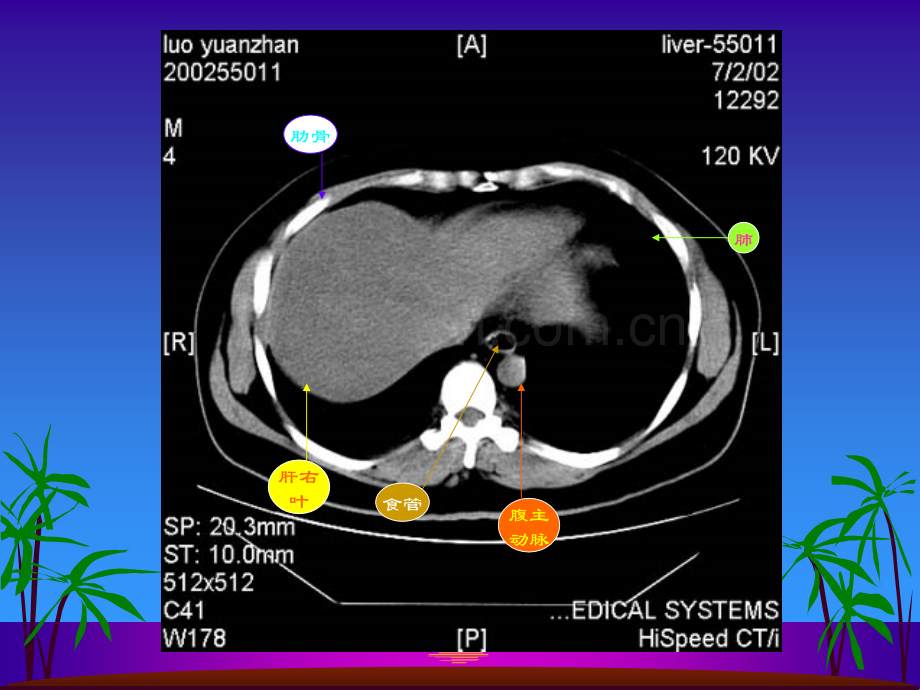

肝右叶横膈肺胸椎脊髓腹主动脉食管肋骨肋骨肝右叶腹主动脉食管肺肝左叶肝右叶腹主动脉胃脾肝尾叶肝右叶尾叶膈脚脾门静脉肝左叶胃肝右叶膈脚腹主动脉脾胆囊胃肝右叶下腔静脉胰腺脾胃腹主动脉肝右叶心脏腹主动脉下腔静脉脊髓食管肺肝左叶肝右叶腹主动脉下腔静脉胃脾脊髓肝左叶及肝左动脉肝右叶及肝右动脉腹主动脉下腔静脉胃脾肝尾叶肝右叶下腔静脉腹主动脉胃脾膈脚肝静脉下腔静脉腹主动脉食道肝右叶下腔静脉肝右叶肝静脉肝左叶腹主动脉胃脾肝尾叶肝右叶下腔静脉腹主动脉门静脉主干肝左叶胃脾肝右叶下腔静脉门静脉腹主动脉膈脚脾胃肝血管瘤CT平扫呈低密度灶,密度均匀,边缘较清。肝血管瘤静脉注入造影剂后CT扫描,动脉期示:病灶由边缘向中心结节状强化,逐渐填满,其密度与同层腹主动脉相似。腹主动脉肾肝血管瘤静脉期示病灶进一步强化填充,呈密度较均的高密度灶,显示更清楚。肝血管瘤2分钟后,平衡期CT扫描示病灶仍呈较高密度,显示清楚,表现为“早出晚归”征肝血管瘤CT平扫示肝脏左右叶普遍增大。静脉注入造影剂后CT扫描,静脉期示肝实质呈不均匀强化。门静脉肝硬化:CT平扫示肝脏左右叶体积缩小,边缘欠平整,肝裂增宽肝裂增宽 肝硬化并门静脉高压,静脉注入造影剂后静脉期CT扫描示:脾门静脉曲张。脾门静脉曲张脾肝右叶肝左叶肝癌CT平扫示:肝脏体积明显增大,边缘不平整,肝实质密度不均,内见结节状、团块状低密度癌灶,边缘模糊,密度不均。肝右叶巨大癌灶肝内结节状癌灶静脉注入造影剂后CT扫描,动脉期示:肝内癌灶不均匀增强,密度增高,其内见肿瘤坏死部分不强化,呈更低密度。癌灶增强,密度增高瘤内坏死部分呈更低密度静脉早显肿瘤血管肿瘤假包膜静脉注入造影剂后CT扫描,静脉期示下腔静脉内癌栓呈低密度充盈缺损表现。肝右叶癌灶腹主动脉静脉注入造影剂后CT扫描,静脉期示:由于造影剂洗脱,肿瘤呈较低密度。本例见癌肿侵犯门静脉,门脉左支受压变形,门脉右支未见显影。门静脉左支受压变形肝内癌灶静脉注入造影剂后CT扫描,平衡期示:肝内癌灶随造影剂进一步洗脱呈低密度表现。本例门静脉左支内还可见稍低密度癌栓。门静脉左支及其内癌栓肝内癌灶 胆囊体积缩小,胆囊壁稍厚。肾胰肝肾静脉腹主动脉慢性胆囊炎CT平扫示:胆囊体积缩小,胆囊后壁见一类椭圆形高密度结石胆囊结石腹水肝胰肠管脾腹水肾正常胰腺CT平扫 胰腺体、尾部胆囊肝右叶脾肠管下腔静脉膈脚腹主动脉正常胰腺CT平扫肝右叶胰头肠管肾腹主动脉下腔静脉 静脉注入造影剂后,正常胰腺CT对比增强扫描胆囊肝右叶下腔静脉胰体胰尾脾肾肠管脾静脉 静脉注入造影剂后,正常胰腺CT对比增强扫描胰头下腔静脉肝右叶腹主动脉肾肠管脾静脉脾急性单纯性胰腺炎CT平扫胰腺肝脾左肾下腔静脉腹主动脉胃急性单纯性胰腺炎CT平扫胰腺脾右肾肝下腔静脉腹主动脉胆囊胃急性单纯性胰腺炎CT平扫胰头胃肝胆囊脾左肾下腔静脉腹主动脉肠管急性单纯性胰腺炎CT对比增强扫描胰腺胃胆囊肝下腔静脉腹主动脉脾静脉左肾脾急性单纯性胰腺炎CT对比增强扫描腹主动脉脾静脉下腔静脉胰头肝胆囊胃左肾脾肠管急性渗出性胰腺炎CT平扫胰腺胃肝脾右肾下腔静脉腹主动脉急性渗出性胰腺炎CT平扫胰腺胃肝脾腹主动脉下腔静脉右肾肾前筋膜增厚胆囊急性渗出性胰腺炎CT平扫胰腺胃胆囊肝右肾下腔静脉腹主动脉肾前筋膜增厚左肾脾慢性胰腺炎CT增强扫描示:胰管扩张胰腺扩张胰管胃胆囊增大肝右肾右肾静脉腹主动脉左肾左肾静脉脾胰腺体积缩小胰腺胃脾左肾肝右叶肝左叶下腔静脉腹主动脉